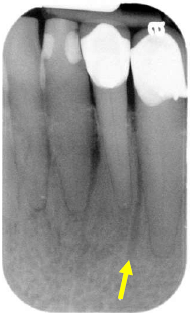

Após analisar a radiografia abaixo, assinale a opção que corresponde à estrutura indicada pela seta.